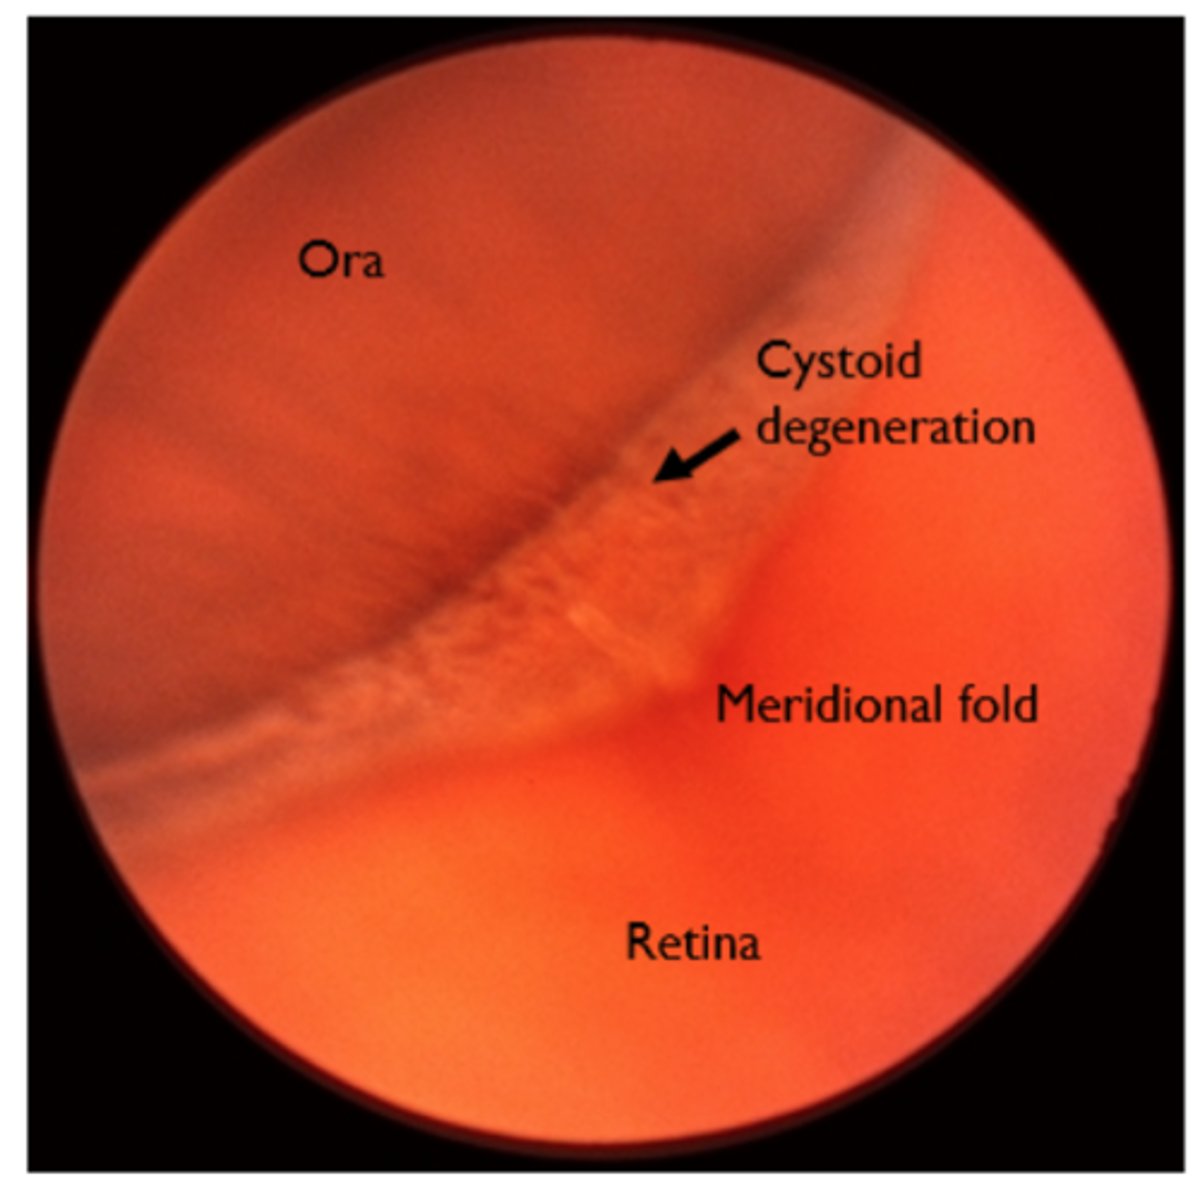

Cystoid degeneration aetiology

Present in ~100% of eyes over 80 years of age (increases with age)

• Tiny vesicles with indistinct boundaries on a greyish-white background

• Usually close to the ora serrata

• May resemble lattice degeneration -cystoid is elevated while lattice is

depressed

• Benign (although possible link with degenerative retinoschisis)